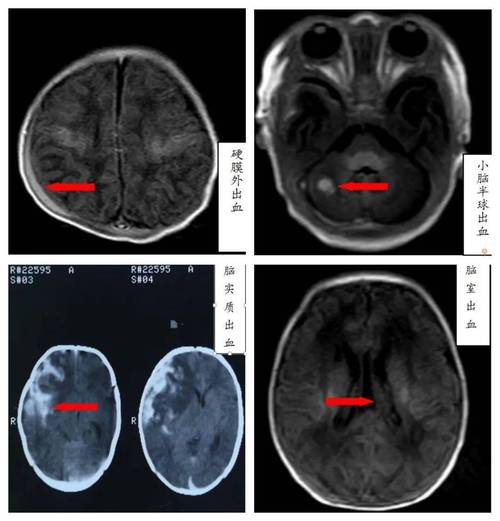

重要提示:在新生儿领域,我们更常使用“新生儿颅内出血”(Intracranial Hemorrhage, IVH)这个总称,蛛网膜下腔出血是其中一种类型,其他还包括脑室内出血、脑实质出血等,不同类型的出血,严重程度和预后也不同。

- 头颅CT(Computed Tomography):

- 对出血的分辨率非常高,能清晰显示出血的部位、范围和量。

- 但有辐射,通常在病情紧急或需要更精确评估时使用。

- 头颅MRI(Magnetic Resonance Imaging):

- 没有辐射,能提供更精细的脑部结构图像,对评估脑损伤的预后价值更高。

- 通常在病情稳定后,为了更全面评估脑损伤情况而进行。